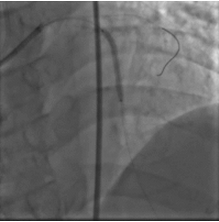

手术过程

取0.014" Runthrough NS导丝通过病变送入高位钝缘支远端(图4),送入Atlantis SR血管内超声导管至左主干远段,未见明确前降支开口影像,0.014" Sion导丝未能通过前降支近段支架内闭塞病变处,换用0.014" ConquestPro导丝成功通过前降支近段支架内闭塞病变送至前降支中段(图5、6),换入0.014" Sion导丝至前降支远端,Sprinter Legend 2.5×15 mm球囊锚定导丝后,再以该球囊成功通过闭塞病变,反复以10~12 atm×5 s扩张(图7)。复查造影显示前降支恢复TIMI 3级血流,前降支近段处残余狭窄50%,中段局限性狭窄70%(图8)。Sprinter Legend 2.5×15 mm球囊以6 atm×8 s扩张前降支中段病变后,送入IVUS导管至前降支中段连续自动回撤示前降支中段心肌桥征象,近段弥漫性纤维斑块形成。植入Buma 3.5×25 mm雷帕霉素药物支架以10 atm×8 s扩张释放(图9),稍前送该支架球囊至两支架交界处以10 atm×8 s再次扩张塑形。行IVUS检查左主干内支架贴壁不良。取Quantum 4.5×12 mm高压球囊至左主干支架内以14~20 atm×8 s扩张塑形(图11),复查造影示支架扩张满意,残余狭窄<30%,血流TIMI 3级,回旋支血流未受影响(图12)。复查血管内超声示支架扩张满意,贴壁良好,支架两端无夹层征象。

图5、6